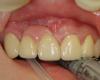

BORA Опубликовано 28 мая, 2011 Поделиться Опубликовано 28 мая, 2011 (изменено) Пациентке удаляли клык....снесли вестибулярную стенку..Возможности заснять нет...схема максимально приближена к реальности....обозначены уровни кости с вестибулярной и небной стенок...размеры дефекта...толщина гребня около 4х...т.е с вестибулярной стороны этакая канавкаРечь об имплантации не идет...Вопрос в эстетикеЧем придать объем?какой лоскут ?http://s001.radikal.ru/i194/1105/fe/b92d925c8c17.jpghttp://s52.radikal.ru/i136/1105/db/1077da388e61.jpg Изменено 28 мая, 2011 пользователем BORA Ссылка на комментарий

BORA Опубликовано 30 мая, 2011 Автор Поделиться Опубликовано 30 мая, 2011 десна 4 мм...все плохо....т.е. вопрос стоит как заместить дефект хотя бы до уровня шеек соседних...Сст предложили....но приживется если поддержки нет..кости то нет?! Ссылка на комментарий